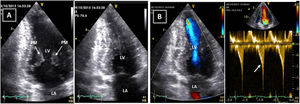

Resting electrocardiogram (ECG) (top) and transthoracic echocardiogram (TTE) (bottom), before detraining. (A) ECG with voltage criteria for LV hypertrophy and marked deep T-wave inversion in leads I, II, III, aVF and V3-V6, with ST-segment depression; (B) TTE (apical 4-chamber view), showing moderate asymmetric hypertrophy, localized at the mid-apical segments of the left ventricle, with maximum wall thickness of 16 mm. LA: left atrium; LV: left ventricle; RA: right atrium; RV: right ventricle.

Case reportA 22-year-old Caucasian male soccer player undergoing a pre-participation exam (PPE) presented a very unsettling ECG (Figure 1), highly suggestive of cardiomyopathy. He was asymptomatic, had a normal physical exam and his family history was negative for cardiovascular (CV) disease and SCD. He had been playing amateur soccer at regional level for ten years, training three days a week (90 min), with a weekly match. The transthoracic echocardiogram (TTE) revealed a nondilated left ventricle with asymmetrical apical hypertrophy (maximum LV wall thickness 16 mm) (Figure 1 and Video 1) and normal left ventricular ejection fraction and diastolic function. On cardiac magnetic resonance (CMR) the maximum apical thickness was 14 mm and the LV cavity had a spade-like appearance during diastole. No late gadolinium enhancement (LGE) was detected (Figure 2). Holter monitoring and treadmill exercise testing were normal (16 metabolic equivalents, no symptoms and no arrhythmias) and genetic testing was negative for the following mutations: MYH7, MYBPC3, ACTC1, TNNT2, TNNI3, TPM1, MYL2, MYL3, CSRP3 and TCAP.

Follow-up assessment was performed four months later. He had reportedly respected our warning and barely exercised in the meantime. While still abnormal, the ST-segment depression and deeply inverted T waves had become less prominent (Figure 3). We repeated the TTE and had a similar impression: although maximum wall thickness in the apex was significantly decreased (10-11 mm) and not diagnostic of HCM, the TTE seemed clearly abnormal, given the small cavity, the abnormal geometry and the apical gradient (Figures 3 and 4 and Video 2).

Resting electrocardiogram (ECG) (top) and transthoracic echocardiogram (TTE) (bottom), performed four months after detraining. (A) The ECG shows a clear improvement of the T-wave abnormalities in the inferior and lateral leads, although the ECG is still abnormal; (B) on TTE, a decrease in both septal and apical LV wall thickness is evident (maximum 11 mm). LA: left atrium; LV: left ventricle; RA: right atrium; RV: right ventricle.